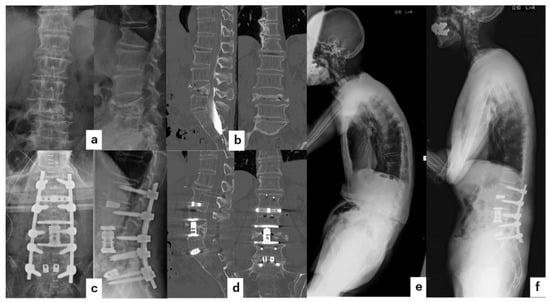

4.1. Case 1